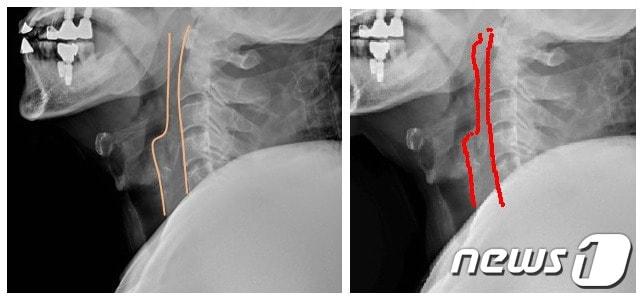

본문 이미지 - 세브란스병원 영상의학과 이영한 교수, 연세대학교 공과대학 황도식 교수가 공동으로 개발한 인공지능(AI)을 이용해 경추(목뼈) 상태를 비교 및 분석한 모습.ⓒ 뉴스1

세브란스병원 영상의학과 이영한 교수, 연세대학교 공과대학 황도식 교수가 공동으로 개발한 인공지능(AI)을 이용해 경추(목뼈) 상태를 비교 및 분석한 모습.ⓒ 뉴스1